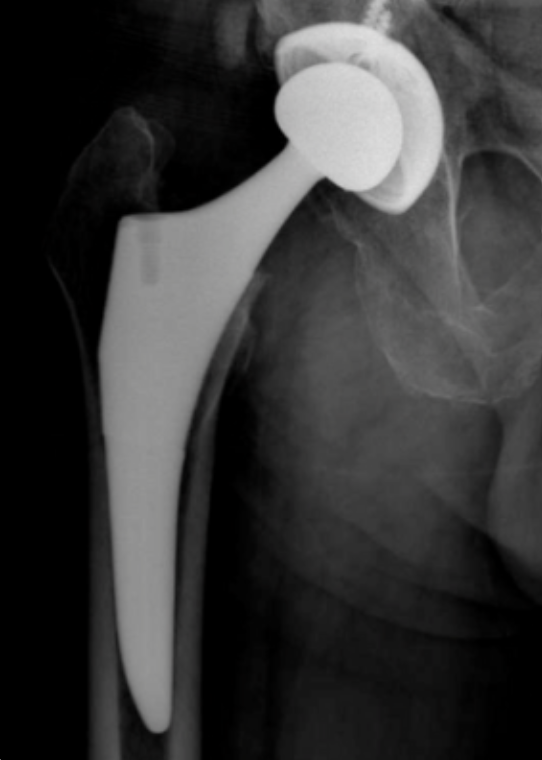

The Klassic® Femur with Aurum® Technology features the same patented geometry and articulation as the Klassic® Femur and offers a revolutionary ballistically bonded titanium nitride (TiN) surface to provide a premium implant without the deliberate addition of common metal sensitizers such as nickel, cobalt, and chromium.

Aurum® is the first step as part of TJO’s multiyear plan to reduce the use of Cobalt Chrome in orthopedic implants; it uses a patented ion beam enhanced deposition (IBED) process to create a well-structured, ceramicized surface layer that is interdigitated with the substrate while preserving the material and geometric properties of the implant.

Titanium is up to 50% lighter than cobalt chrome, and the Aurum® Femur offers an implant that more closely replicates the weight of native bone.